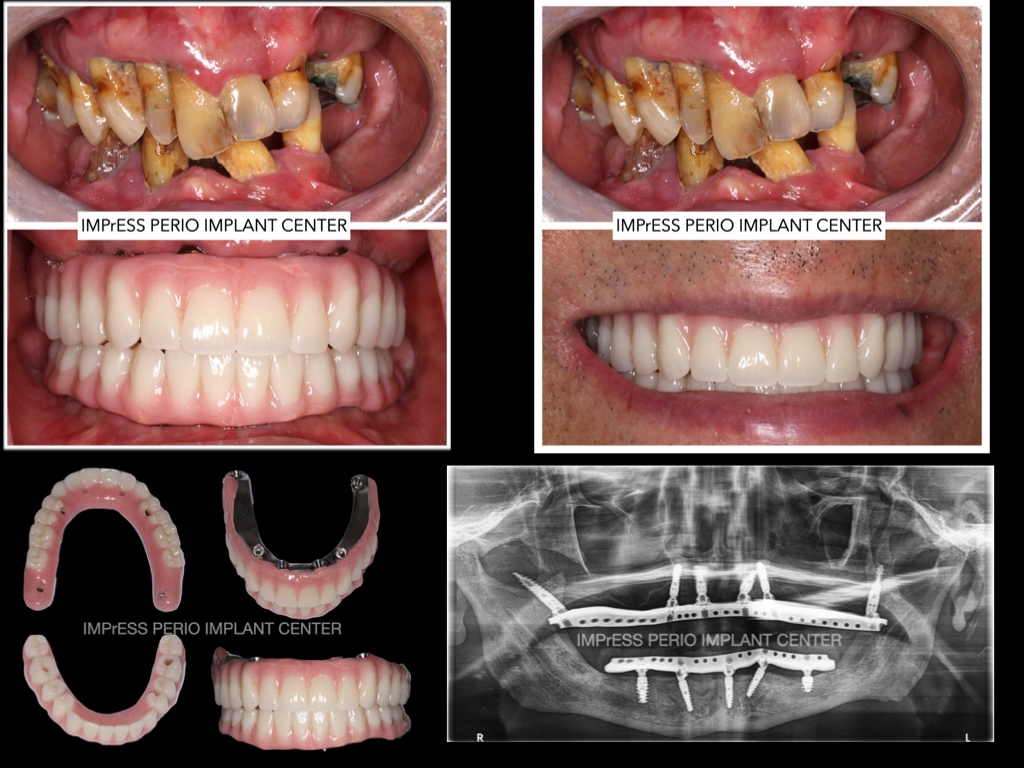

All on X implant Full Mouth Implant Reconstruction All on 4 Implants IMPrESS Perio Implant Center Vancouver Burnaby Periodontist Prosthodontist Implant Specialist Dr. Noroozi Periodontist Implant Specialist

All on 4 All on 6 implants Teeth in a day Full Implant Denture IMPrESS Perio Implant Center Dr. Noroozi Vancouver Implant Specialist

All On X Full Mouth Implants Fixed Teeth IMPrESS Perio Implant Centre Dr Noroozi Burnaby Vancouver BC

Teeth in one day full mouth dental implants Implant teeth impress perio implant center Dr. Noroozi

Step 1: If you have lost all of your teeth in one or both of jaws and require the most natural-looking solution, the permanently anchored dental implant bridge on several dental implants is the answer when the prerequisites are met.

Step 2: For a permanently anchored dental implant bridge, several dental implants are installed to form a good foundation. Because the dental implants are anchored in the jawbone, they stimulate the bone tissue and help to maintain healthy bone levels and facial structure

Step 3: The abutments are attached to the dental implants and the bridge is fitted in place. All dental work is performed according to your prerequisites and wishes.

Step 4: The dental implant bridge is now in place. It looks and functions like normal teeth. You can now eat whatever you like and laugh without having to worry about the prosthesis falling out.